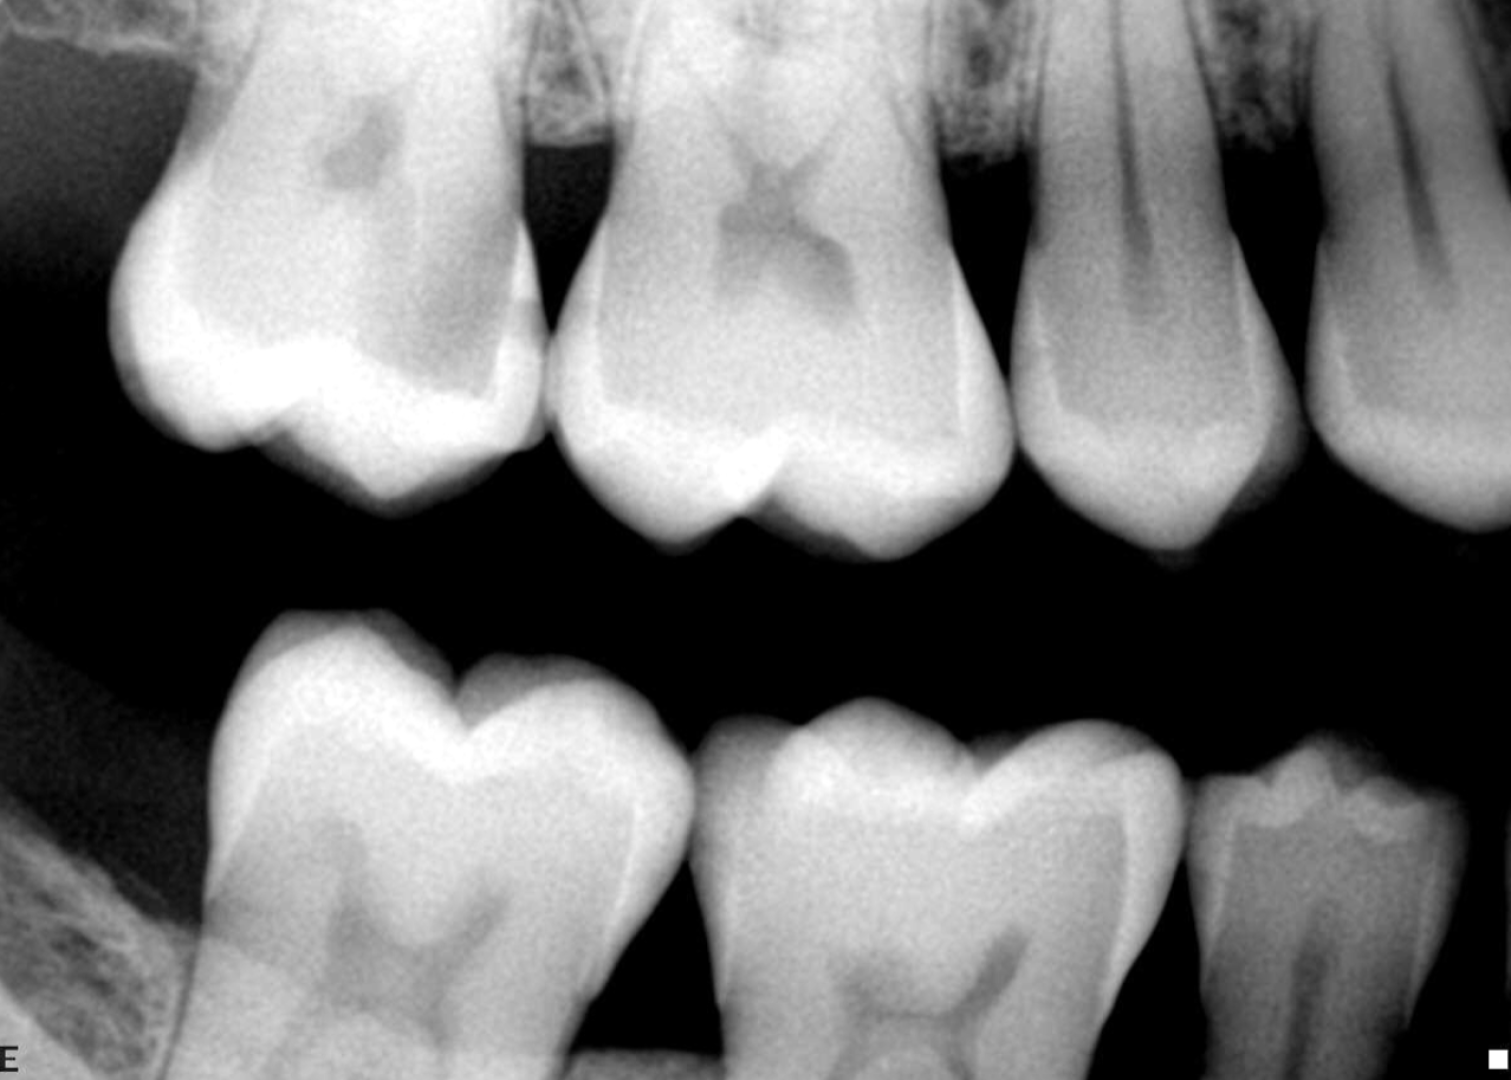

Dental Pearl is an advanced AI-powered dental imaging platform that analyses your dental X-rays in real time. Trained on millions of clinically validated images, it identifies areas of concern — such as tooth decay, bone loss, infections, and early signs of gum disease — with exceptional precision.

AI highlights areas that may require attention, reducing the risk of missed findings and helping your dentist deliver the most accurate, evidence-based diagnosis possible.

With Dental Pearl, you can see exactly what your dentist sees. The AI visually highlights findings on your X-rays, helping you understand your oral health and treatment options with complete transparency.

By catching early signs of decay or bone changes, AI allows us to intervene sooner — saving you from more complex and costly treatments later on.